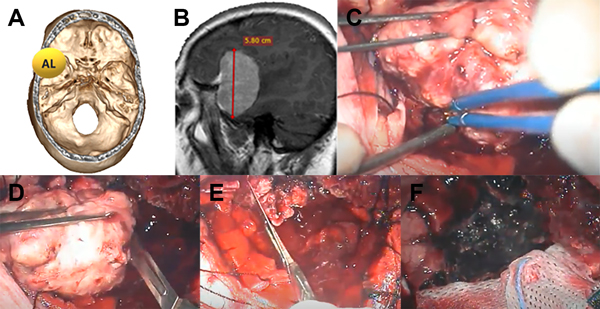

Se analizaron características epidemiológicas y clínicas del paciente, y características del tumor ya sea localización, tamaño, imagenológicas y si tiene embolización previa o no. El grado de resección se midió con la clasificación de Simpson tradicional y también se dividió en resección total (Simpson I, II y III) y subtotal (Simpson IV y V) (Figura 1).

Figura 1: Imágenes representativas de paciente operado de meningioma de base de cráneo anterior de surco olfatorio. A: secuencia T1 con contraste de resonancia magnética, corte axial. B: Misma lesión corte coronal C: corte coronal de imagen posoperatoria. D: abordaje y craneotomía realizada.

Figura 3: Paciente con meningioma de base de cráneo anteromedial (AM) (1 punto), tamaño menor de 5 cm (1 punto), sin invasión ósea (1 punto), puntaje total: 3, alta probabilidad de resección total. A: localización de lesión en base de cráneo. B: reconstrucción 3D con abordaje. C: resonancia con contraste corte sagital prequirúrgica. D: resonancia con contraste corte sagital posquirúrgica con resección total.

Figura 4: Paciente con meningioma de base de cráneo anterolateral (AL) (1 punto), tamaño más de 5 cm (2 puntos) sin invasión ósea (1 punto), total: 4 puntos, moderada probabilidad de resección total. A: localización de lesión en base de cráneo. B: resonancia con contraste corte sagital prequirúrgica. C: imagen intraoperatoria en donde se observa meningioma con plano aracnoideo. D: vaciamiento y reducción de tamaño con bisturí hoja 11. E: resección parcial de duramadre y coagulación de la misma. F: lodge quirúrgica sin remanente tumoral, resección Simpson 2.